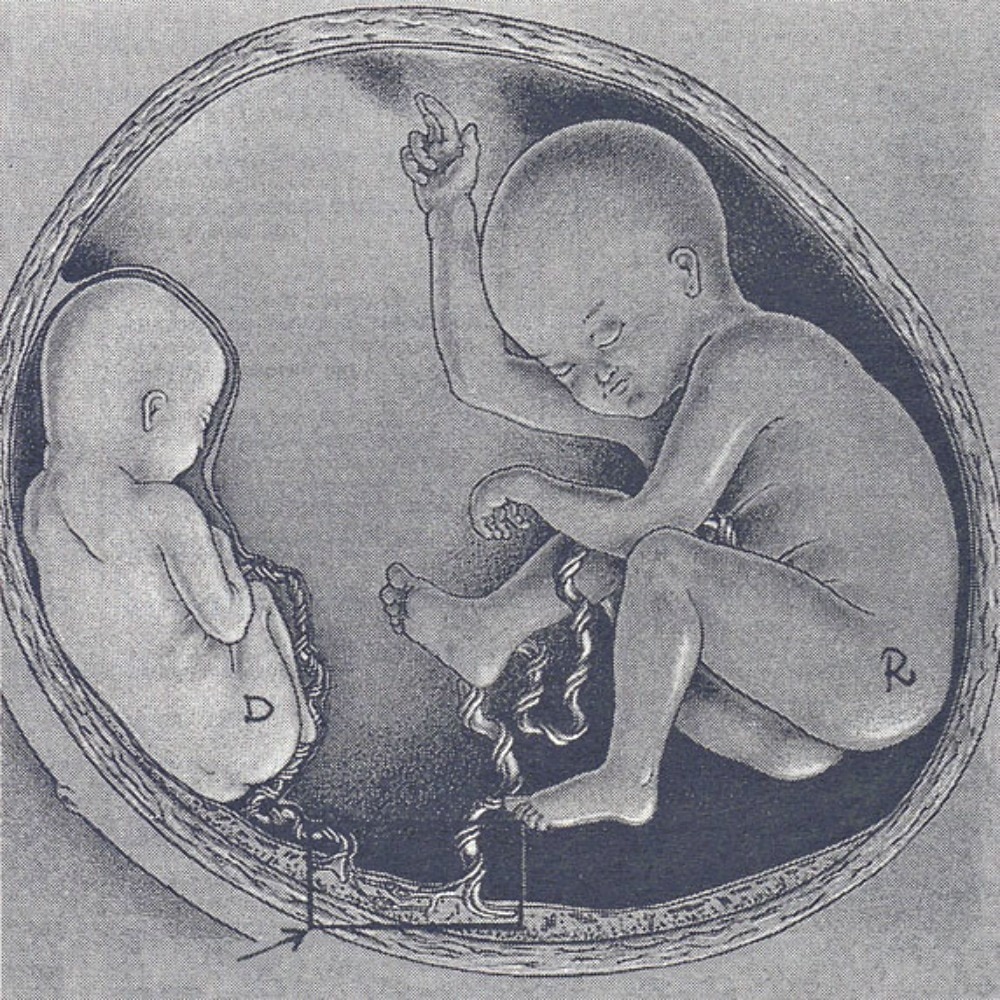

Иконки и символы, связанные с эмбрионом

Раздел: Образы вокруг